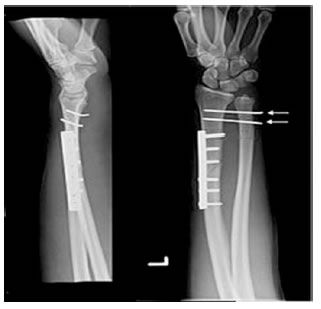

2. Phẫu thuật:

- Đối với gãy xương hở, gãy chéo vát, nắn chỉnh không hết di lệch hoặc di lệch thứ phát trong bột.

- Kết hợp xương nẹp vít xương quay, nếu khớp quay trụ dưới không vững thì xuyên 02 định kirtschner tư thế cẳng tay ngữa trong 4 tuần, với cẳng bàn tay trong nẹp bột

Chỉ định: Gãy thấu khớp, gãy hở, kèm theo gãy xương cổ tay, tổn thương mạch máu thần kinh, điều trị bảo tồn thất bại, gãy 2 tay.

Phương pháp: xuyên kim, kết hợp xương nẹp ốc, cố định ngoài.